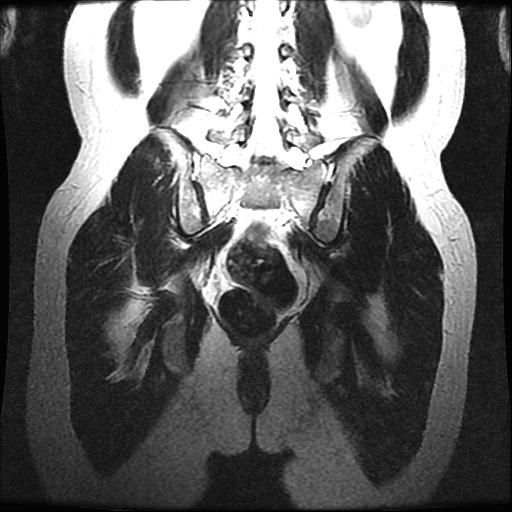

강직성척추염 의심(xray 및 mri 첨부)

인터넷 검색 후 강직성척추염을 알게 되어 말씀 드렸더니 스트레칭??을 해보시고 아닌 것 같은데 걱정이 된다고 하니 x-ray 및 mri를 찍어보자고 하셨습니다. (유전자검사는 채혈 후 대기 중)

xray 및 mri상에도 의심소견이 없다고 하셨는데

사진으로 염증이 있는지 확인 부탁드립니다.

올려주신 엑스레이나 MRI를 참고할 때, 또는 진료시 스트레칭을 통한 허리 및 천장관절의 유연선 평가와 개인에 따라 다르지만 대표적인 강직성 척추염의 증상이 크게 없는 것으로 보아 발생 가능성이 낮을 수 있습니다.